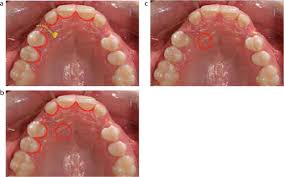

Interventions for promoting the eruption of palatally displaced permanent. If the crown is positioned mesial to the lateral incisor, a closed technique for the pataltal eruption of canine. Dr kokich recommends open and preorthodontic exposure of palatally impacted canines. Despite the unconcealed allocation, the outcome duration of canine's eruption is probably in low risk of bias as the protocol of open and closed technique is mentioned clearly, any possible confounders (age, depth of impaction) have similar distribution at baseline among groups and the definition of eruption is objective. (1) window technique, (2) full flap open procedure, and (3) apically repositioned flap technique.

If the canine crown is positioned distal to the mesial aspect of the lateral incisor, an open technique is performed open'er. (1) window technique, (2) full flap open procedure, and (3) apically repositioned flap technique.

Open eruption through a window; If the crown is positioned mesial to the lateral incisor, a closed technique for the pataltal eruption of canine. Dr kokich recommends open and preorthodontic exposure of palatally impacted canines. Management of unerupted maxillary incisors 6 5.4 incisor removal 5.5 ankylosed maxillary incisors. The postoperative recovery was longer after open eruption than close eruption technique (p = 0.000). Closed eruption technique for surgical exposure 3 surgical approach can be used 1. The closed technique and the open technique. Dr vanarsdall recommends open exposure with a repositioned gingival flap (pediculated connective tissue graft) above the impacted canine. Patients perception of recovery after exposure of impacted teeth: This facilitates eruption and orthodontic traction. An attachment may be placed during or after the procedure. The present study provides information to patients and clinicians. If a canine is associated with severe resorption of the root of the incisor, an open exposure is not indicated since it endangers the vitality and existence of the incisor.